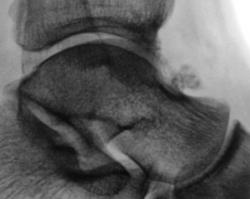

Шпоры пяточной кости (и в месте прикрепления ахиллова сухожилия, и в месте прикрепления подошвенного апоневроза) в сочетании с выраженным окостенением подошвенного апоневроза.( По Д.Г. Рохлину-это локальные проявления преждевременного старения костно-суставной системы.)

Тендиноз в области пяточного бугра. Окостенение подошвенного апоневроза может быть травматического характера, может связанного с профессией.

Несколько раз наблюдал переломы остеофитов, причем с соответствующей клиникой, здесь вероятно именно такой случай. Интересно - срастется ли?

Спасибо за комментарии! Я в заключении написал, что выше отметили коллеги: "Оссификация подошвенного апневроза".Цель демонстрации: за 25 лет работы столь выраженные изменения, вижу впервые.Не уверен, что есть перелом оссифицированного апоневроза.

У меня тоже недавно был пациент с "локальными окостенениями" подошвенного апоневроза.